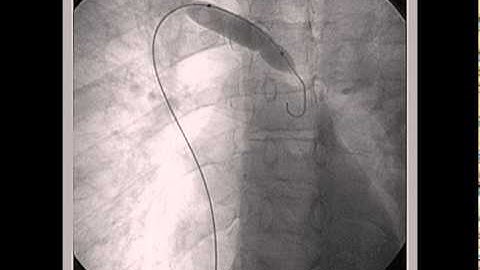

Azygos Continuity and Persistent Left SVC